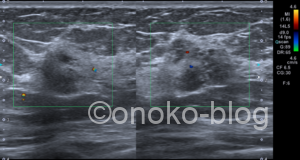

エラストグラフィーは

一部で歪みの低下がある…ような…

こちらの受診者様は3年前も当院でエコーを受けていただいていたので 画像を確認します。

エコー機が違うので、見え方が少し異なっているのか?

でも内部エコーが変化しているような…

カラードプラはあまり変わらないですね

このぼやっとして見える感じ…

小葉癌?DCIS?